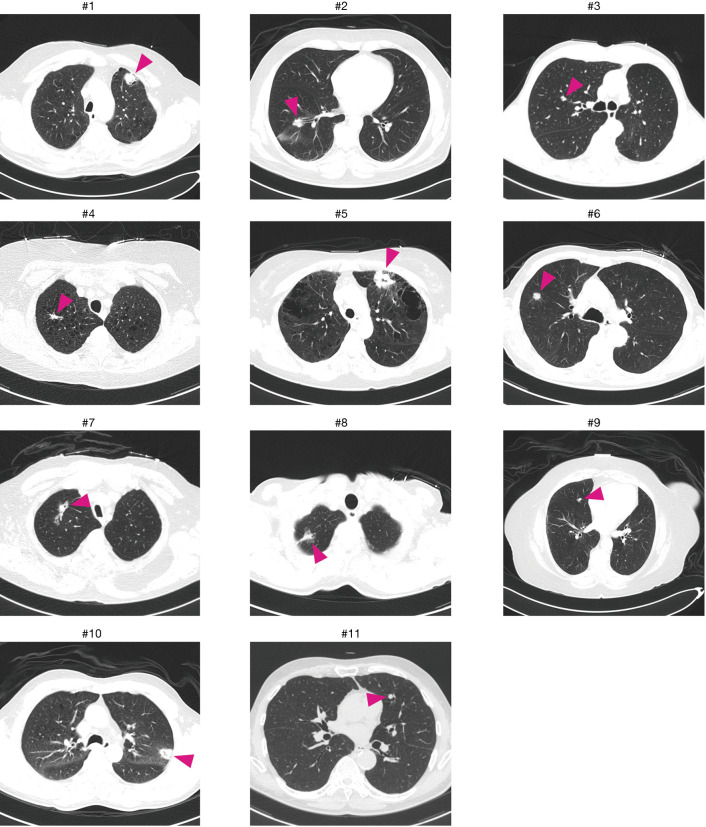

A total of eleven patients were enrolled between October 2013 and August 2017. The original target was 20 patients over 2 years; slow accrual prompted the decision to close the study before reaching this sample size goal. The patient characteristics and lesion information are summarized in Table 1. The details of each patient and diagnostic outcomes are listed in Table 2. There were seven male and four female patients with a median age of 67 years (range, 57–90 years). The mean size of pulmonary nodules on CT was 2.1 cm (median, 2.0 cm; range, 1.0–4.4 cm). Nine pulmonary nodules (82%) had a positive CT bronchus sign. Seven pulmonary nodules (64%) were located in the peripheral third lung field. The mean pleural surface-to-pulmonary nodule distance was 1.9 cm (median, 1.9cm; range, 0-5.3 cm). Representative CT images of the pulmonary nodules are shown in Figure 2. Seven cases underwent conventional bronchoscopy as the first procedure. Biopsy tools used for each case are shown in Table S1. Ten out of eleven patients underwent surgery for diagnosis and treatment. One patient (case #4) was surveilled by imaging alone, with a total of three CT scans over two years; the nodule was clinically diagnosed as benign due to diminishing size.

Figure 2.

Computed tomographic axial images of the chest in all cases. Magenta arrow heads show locations of the target lesions.